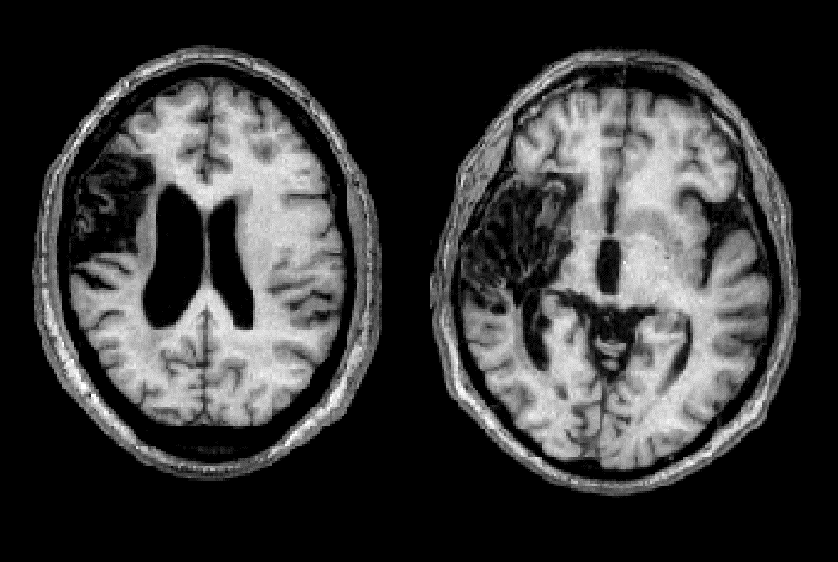

Chẩn đoán vị trí tổn thương

Dựa vào các dấu hiệu thần kinh khu trú

Phân làm 2 nhóm:

- Tuần hoàn trước: từ động mạch cảnh

- Tuần hoàn sau: từ động mạch sống nền

Hình: Ranh giới phân bố các động mạch não chính (trước, giữa, sau)